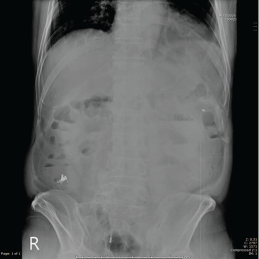

Ekip quyết định chụp X-quang bụng cấp cứu. Kết quả không thấy liềm hơi dưới hoành, có thể loại trừ thủng; nhưng triệu chứng đau khu trú kèm ¾ yếu tố nguy cơ (vị trí manh tràng, kích thước ≥ 40mm, thời gian can thiệp ≥ 90 phút) nên chẩn đoán hướng đến PECS. Bệnh nhân tiếp tục được xử trí bảo tồn: nhịn ăn, kháng sinh, dinh dưỡng tĩnh mạch và theo dõi sát.